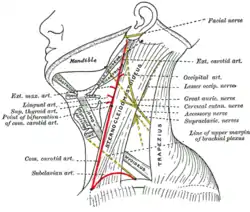

Superficial dissection of the left side of the neck, showing the carotid and subclavian arteries. | |

Diagram showing the origins of the main branches of the carotid arteries.